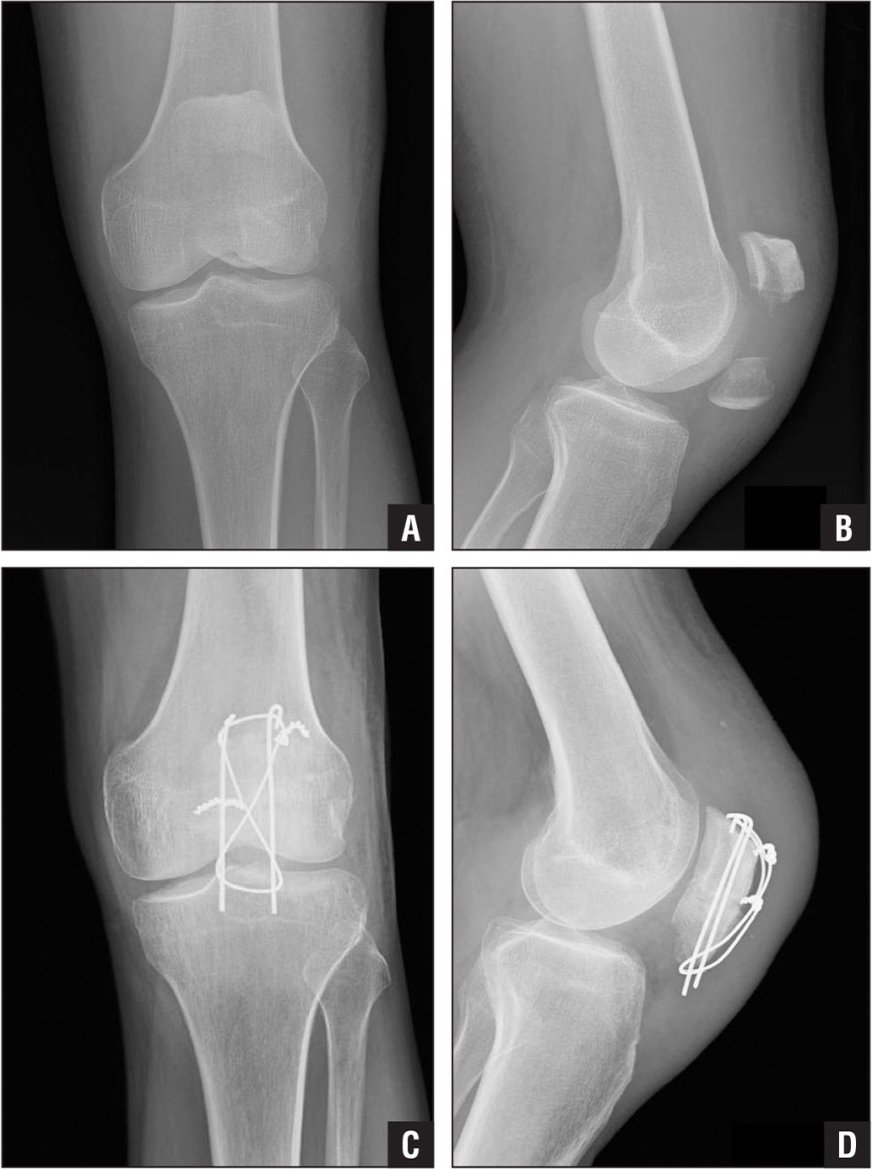

Upload Date: March 31, 2019 Full Size Image Dimensions: 1033 × 1386 Image Parent Post: Κατάγματα κάτω άκρου

6a.Εσωτερική οστεοσύνθεση κατάγματος επιγονατίδας με ταινία ελκυσμού